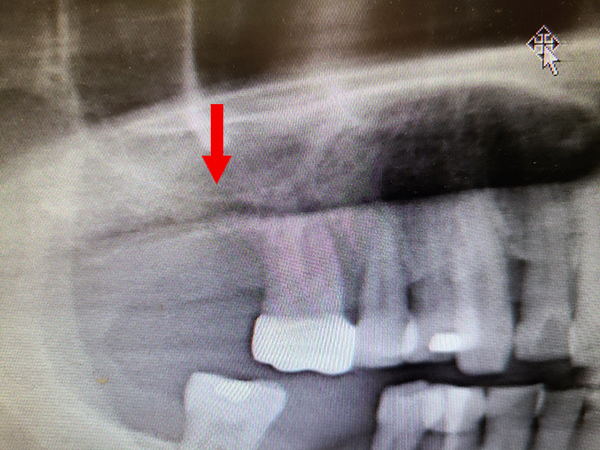

鼻竇破損後修補並進行上顎竇提升術之案例

病人於外院進行彈夾牙治療後牙根斷裂,合併鼻竇穿孔,鼻竇黏膜嚴重感染。

- 紅色箭頭:下方牙齒牙根斷裂,鼻竇黏膜感染增厚。

- 黃色箭頭:移除患齒後進行清創,拔牙後使用膠原蛋白修補,兩個月後恢復清澈鼻竇(影像區為黑色)。

- 綠色箭頭:鼻竇恢復健康後,進行上顎竇提升手術補骨,恢復上顎竇正常骨量,準備進行人工植牙手術。